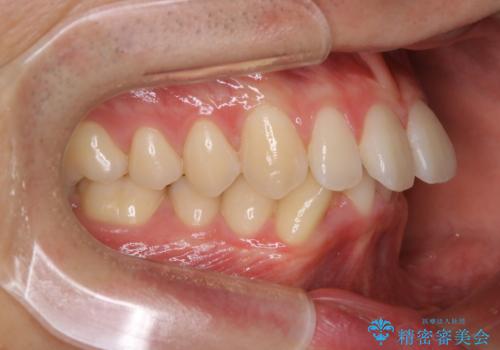

- 口元の突出感は気にならないが、上の前歯の角度と、下の前歯のがたつきが気になるとご相談にいらした方です。なるべく費用や治療期間を抑えて治療したいとのご希望に合わせて治療を計画しました。

この患者様への治療方針として、奥歯から少しずつ歯を移動させる方法と、歯をわずかに削って並べる方法とをご提案しました。短期間での治療を望まれたため、歯をサイズダウンさせて歯を並べました。わずかではあるものの、削った歯は元には戻せないことを十分ご説明し、ご理解ご了承を頂いた上で治療を行いました。